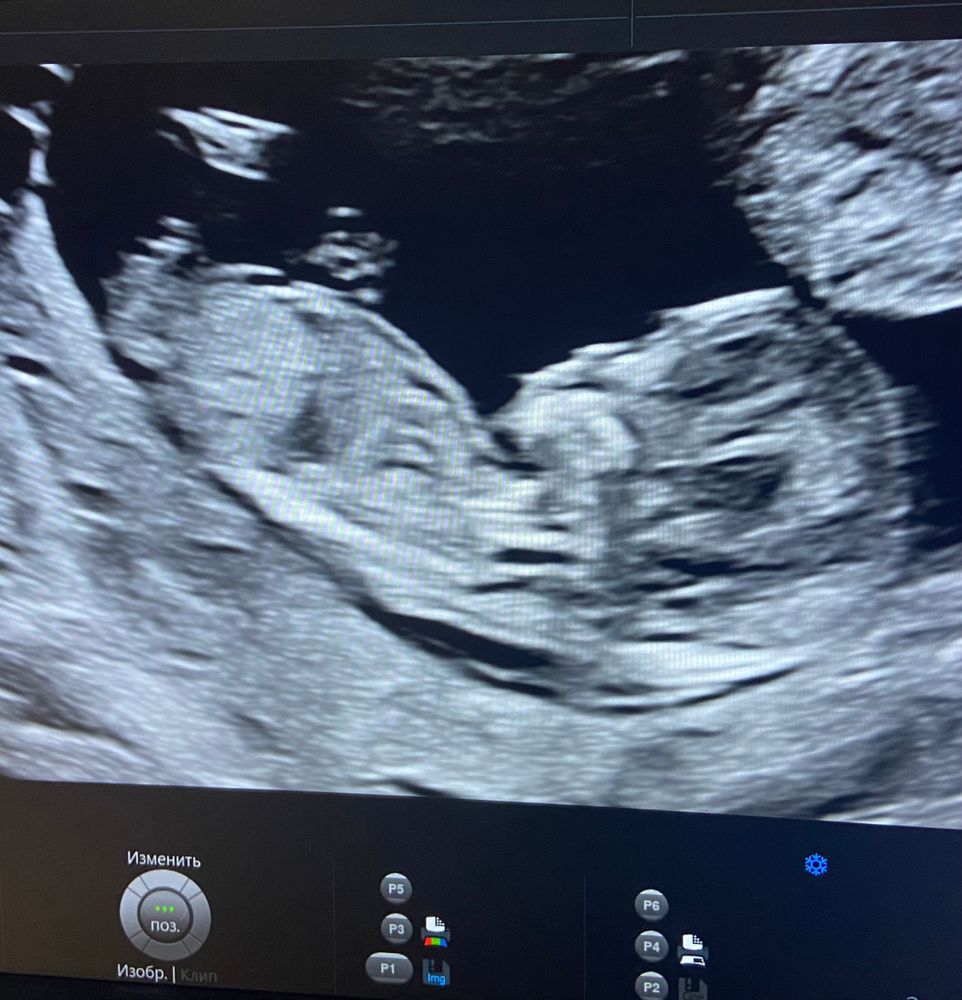

Сегодня прошла первый скрининг на сроке 12.1, по УЗИ все в норме, жду теперь кровь в понедельник!

Доктор про пол ничего не сказала, но, может, кто из опытных девочек что-то поймёт по фото!)

Фото, конечно, так себе, но я возьму смелость и предположу с большей долей вероятности, что это дама.) как то на парня меня не тянет

Так вроде ж полового бугорка не видно тут, так что про не предположить. Но формой головы похож на мальчика)